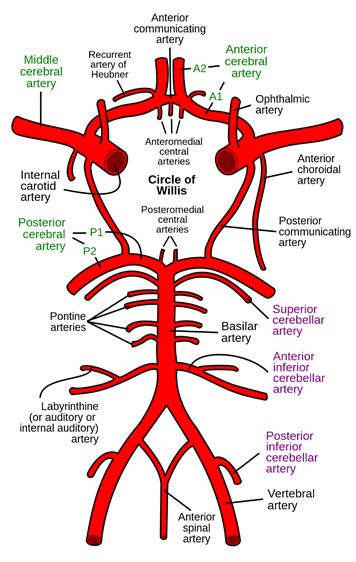

Intracranial vessels

Posterior

circulation

Artery of Percheron – a variant

of the thalamoperforate arteries